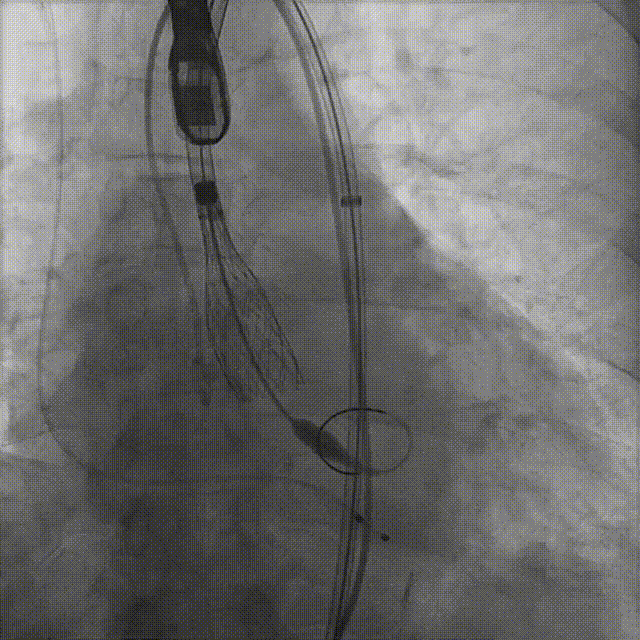

患者病史 体检发现心脏瓣膜病半月余,平素无症状 ,有高血压病史。 后来院复查诊断为:主动脉瓣狭窄(重度)、先天性主动脉瓣二叶瓣畸形、心室肥厚、升主动脉扩张心功能 I 级(NYHA 分级)、高血压病 2 级(极高危)。 术前 CT:Type0型二叶瓣,瓣叶增厚,无钙化,类风湿性;瓣环径25.6mm,LVOT稍收窄,瓣环水平夹角66.6°,轻微横位心;左右冠开口高度可,瓣叶不长,无冠脉风险;心室收缩末内径约32mm,室壁增厚;外周入路无明显迂曲,无钙化、双侧内径可、双股中分叉,右侧为主入路能够支持20F大鞘通过。 造影角度及入路:LAO 6° CAU 13° 手术策略 采用右侧股动脉为主入路,左侧为辅助入路,常规穿刺。推荐使用20球囊预扩,预装TAV29瓣膜,初始定位对齐瓣环上0mm开始释放。 手术过程 20号球囊预扩无明显腰征 输送器过弓跨瓣顺滑 80%工作位观察 术后造影,瓣膜释放位置良好,无瓣周漏 术后超声:人工生物瓣释放后形态满意,瓣叶开放、关闭活动良好,无瓣周漏;跨瓣血流速度降至 2.5m/s,平均压力梯度6mmHg,符合手术预期。 Prostyle A®预装干瓣——“刚柔并济”助力临床最优化解决方案: 丝滑过弓能力:Prostyle A®短瓣架设计联合远端超滑亲水涂层,即使没有联合使用snare,都可以柔顺过弓,该例横位心的患者更好的展现了输送系统的柔顺性; 平衡的径向支撑力:该例患者Type0型二叶瓣,术后形态展开良好且无瓣周漏,在横位心等复杂情况下实现稳定锚定。 80%可回收设计:80%工作位观察,起搏时间更短,对患者损伤减少到最小,也利于术中精准调整瓣膜位置,保证术后效果。